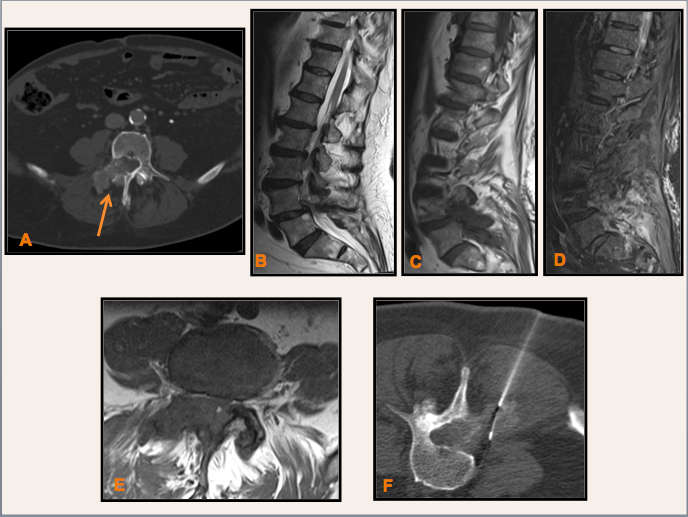

Varón de 82 años sin antecedentes personales conocidos, excepto Gammapatia monoclonal, que se realiza TC tóraco-abdómino-pélvico para descartar adenopatías. Se identifica lesiones líticas en elementos posteriores de L4 y también en L5, extensión intraraquídea, así como componente de partes blandas adyacente; sin adenopatías de tamaño significativo. Dados los hallazgos de la TC, se recomienda RM lumbar.

A: Imagen axial de TC abdominal con ventana de hueso dónde se observa lesión lítica polilobulada en elementos posteriores derechos de L4 con extensión intraraquídia a este nivel; sin otros hallazgos de interés. B: Secuencia T2 sagital de RM lumbar que demuestra lumbodiscartrosis difusa y lesiones focales en L4 y L5. C: Secuencia T1 sagital de RM lumbar dónde se observan lesiones hipointensas en lámina y articulación interapofisaria derecha de L4 y también, aunque en menor grado, en L5. D: Secuencia STIR sagital de RM lumbar dónde las lesiones en L4 y L5 muestran hiperseñal franca. E: Secuencia T1 axial de RM lumbar centrada en L4 con hallazgos superponibles a la TC abdominal. F: Se realizó biopsia percutanea de la lesión derecha de elementos posteriores de L4 con trucut del 19G guiada por TC fluoroscopia.

Tofo gotoso lumbar

- La gota es una enfermedad metabólica común, pero se diagnostica con poca frecuencia en el esqueleto axial, con menos de 25 casos reportados en la literatura.

- Los tofos gotosos se asocian con erosión y destrucción ósea, depósitos intra y extra-articulares de cristales y afectación de elementos posteriores de la columna vertebral así como de los tejidos blandos paravertebrales.

- El principal diagnóstico antes de la biopsia en nuestro caso, era el de mieloma múltiple.

- Los hallazgos de RM específicos mostraron que todas las lesiones son iso/hipointensas en T1 con intensidad variable en T2.

- En la TC los tofos gotosos miden alrededor de 160 UH debido a cristales de urato monosódico.